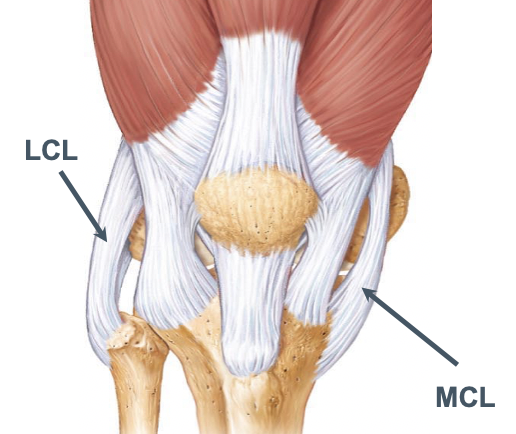

Collateral ligaments of the knee

A

Lateral (fibular)collateral ligament (LCL)

- cord-like, extracapsular ligament

- lateral femoral condyle –> fibular head

- not attached to lateral meniscus

Medial (tibial) collateral ligament (MCL)

- broad, capsular (intrinsic) ligament

- medial femoral epicondyle –> medial tibial condyle

- attached to medial meniscus at midpoint

- more commonly injured than LCL

Both ligaments prevent rotation and lateral flexion in the coronal plane.